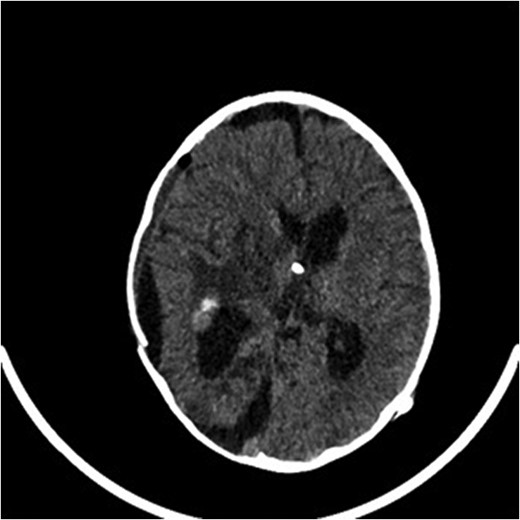

In February 2014, a 5-year old girl presented to the emergency department with a 1-day history of a right temporal swelling, on a background history of vomiting for 5 months. The vomiting was initially associated with motion but progressed to non-motion–related sickness with multiple episodes of vomiting per day, usually subsiding by the afternoon. The patient did not complain of headaches or visual disturbance and did not have any problems with balance or gait. A full neurological examination and examination of all other systems showed no abnormal findings (Figs 1–3).

A computed tomography brain showed a large right temporoparietal cystic solid lesion with calcification and mass effect resulting in midline shift. A preoperative magnetic resonance imaging (MRI) brain and spine showed an enhancing lesion that extended to the occipital lobe, measuring 7 cm in maximum diameter (Fig. 1). A cystic lesion, measuring 5 × 8 cm was also identified posterosuperiorly. The medial part of the tumour extended to the thalami and lentiform nucleus. No spinal metastases were found.